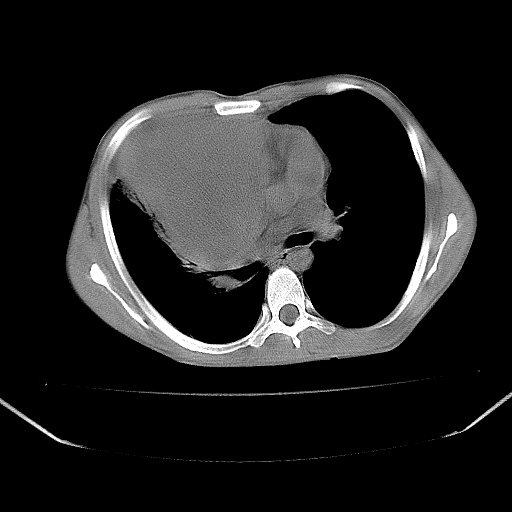

以下是引用zjzjr在2008-7-20 12:57:00的发言:[br]考虑为生殖源性肿瘤(内胚窦瘤),侵袭性胸腺瘤可能性大;右侧少量胸腔积液。

以下是引用xinliheng001在2008-7-20 21:17:00的发言:[br]右纵隔巨大分叶状软组织均质密度肿块,右上肺叶受压明显,纵隔右移、胸膜受累有少量积液和结节样增厚。应增强扫描一定会有更具诊断价值的信息。

以下是引用xinliheng001在2008-7-20 21:17:00的发言:[br]右纵隔巨大分叶状软组织均质密度肿块,右上肺叶受压明显,纵隔右移、胸膜受累有少量积液和结节样增厚。应增强扫描一定会有更具诊断价值的信息。